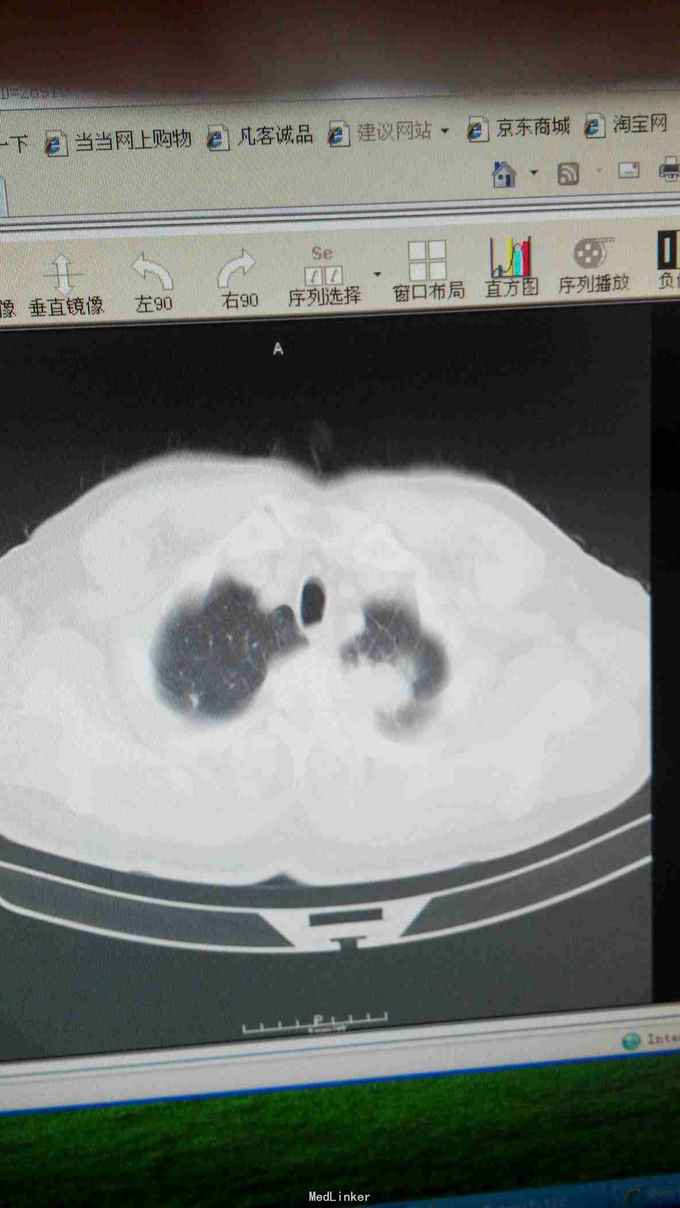

左肺癌化疗后,患者于2015年2月出现咳嗽咳痰,自行口服药物治疗,未见好转,于山西省肿瘤医院CT:左肺上叶肿物,考虑肺癌,周围型,病理示:左肺腺癌,给予(长春瑞滨40mgd1~2+顺铂30mgd1-4)化疗4周期,患者不愿再行静脉化疗,

左肺呼吸弱,CT示:左肺上叶占位。

左肺癌化疗后,2015年7月行细胞免疫治疗及粒子植入术

50天复查